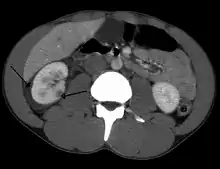

Abdominal trauma resulting in a right kidney contusion (open arrow) and blood surrounding the kidney (closed arrow) as seen on CT

Kidneys

A large hematoma (closed arrow) of the left kidney (open arrow)

The kidneys may also be injured; they are somewhat but not completely protected by the ribs.[6] Kidney lacerations and contusions may also occur.[13] Kidney injury, a common finding in children with blunt abdominal trauma, may be associated with bloody urine.[13] Kidney lacerations may be associated with urinoma or leakage of urine into the abdomen.[4] A shattered kidney is one with multiple lacerations and an associated fragmentation of the kidney tissue.[4]